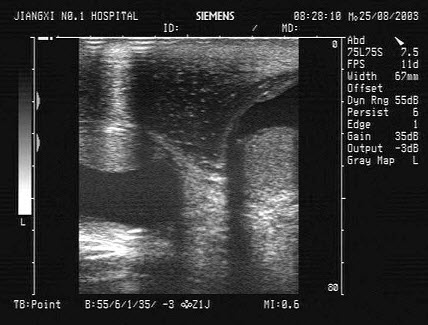

18、单项选择题

女性,41岁,有阵发性高血压病史,超声检查如图所示,该病例最可能诊断()

A.腺瘤

B.肾脏肿瘤

C.嗜络细胞瘤

D.髓样脂肪瘤

E.肾上腺转移瘤